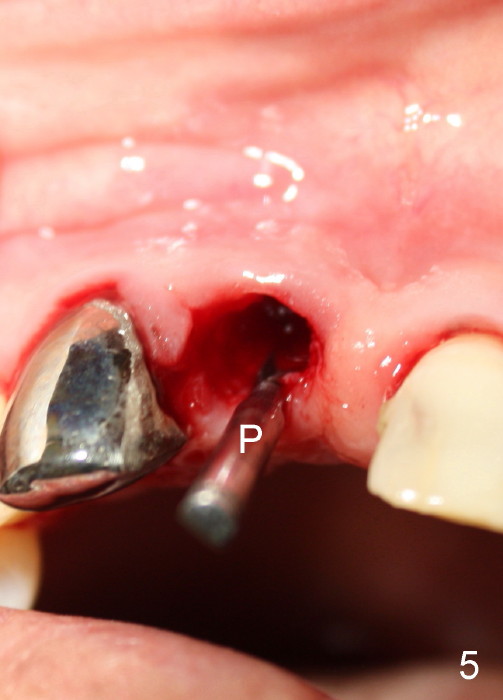

A 64-year-old lady requests replacing #7 and 8 crowns (Fig.1,2). When #8 is extracted, the labial plate is found to be missing (Fig.3). Following 2 mm pilot drill (Fig.4,5 P), 3.8 mm tap drill (Fig.6,7 T) and 4.5x14 mm implant (Fig.8 I) and 4.8 mm abutment (Fig.9 A), corticocancellous bone is harvested from the left tuberosity and placed in the labial gap of the socket (Fig.10 G). Collagen dressing is placed over the bone graft (Fig.11 C). The former is secured in place by an immediate provisional (P).